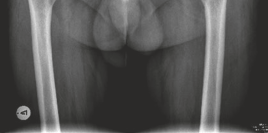

Standard preoperative radiographs included an anteroposterior (AP) pelvis centered over the symphysis pubis with 15 degrees of internal rotation of the lower extremities to profile the femoral necks, alongside true lateral and Dunn lateral views of both hips.

The AP Pelvis radiograph demonstrated severe, bilateral tricompartmental joint space narrowing. The left hip exhibited complete obliteration of the superior and axial joint spaces with bone-on-bone articulation. Subchondral sclerosis was prominent bilaterally, accompanied by marginal osteophyte formation at the femoral head-neck junction and the acetabular rim. Large subchondral cysts (geodes) were visible in the superior weight-bearing dome of the left acetabulum.

The lateral view of the left hip confirmed the loss of sphericity of the femoral head, extensive anterior and posterior osteophytosis, and severe joint space collapse.

The lateral view of the right hip demonstrated similar but slightly less advanced degenerative changes, with marked loss of anterior joint space and reactive subchondral bone formation.